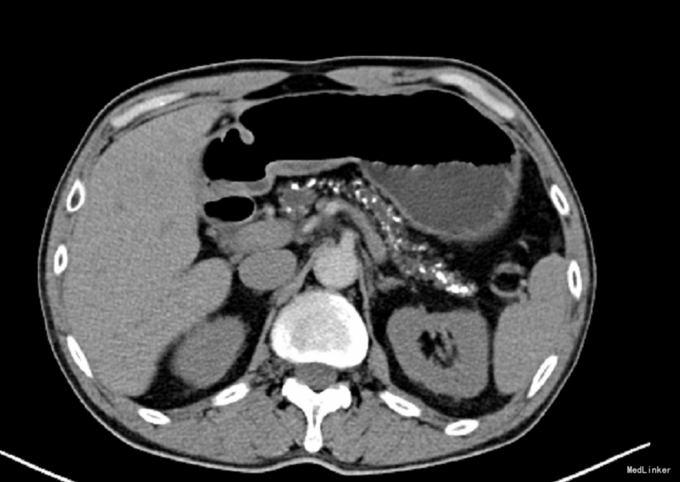

腹平软,上腹部轻度压痛,无反跳痛,肝脾肋下未触及,墨菲氏征阴性,移动性浊音阴性,肠鸣音4次/分。辅助检查:(2014-12-10 )行US检查提示:肝VIII段血管瘤。慢性胰腺炎考虑。胆囊、脾脏未见明显异常。(2014-08-11)CT检查提示:慢性胰腺炎,肝VIII段条状密度异常,考虑血管畸形。(2014-12-25)MRI检查提示:MRCP示胰管扩张,肝内外胆管轻度扩张。胆囊增大。(2015-04-07)CA199 56.8U/mL。↑

初步诊断: 慢性胰腺炎。排除相关手术禁忌症后,在全麻下行“[腹腔]胰十二指肠切除+胆道镜胰管探查术”。